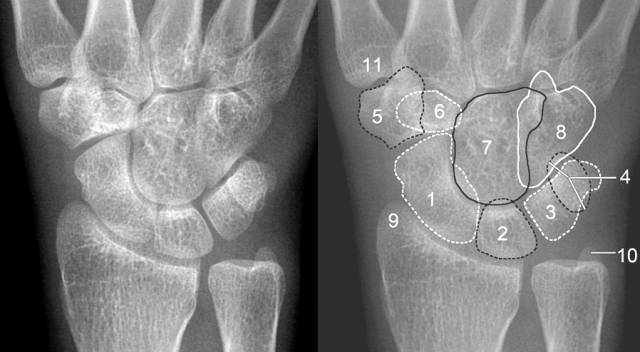

腕关节正侧位(右侧)

正常腕关节

成人腕关节外伤x线诊断

(1)正位片上:前后排腕骨后缘形成光滑的弧线;前后排腕骨不重叠;头,钩